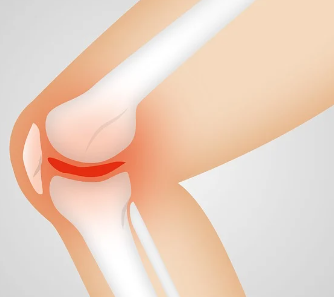

류마티스 관절염은 뼈와 관절, 근육, 힘줄 등을 연결하는 연조직의 염증으로 인해 발생하는 질환입니다. 나이가 들수록 발생 확률이 높아지며, 여성이 남성보다 발생률이 높은 편입니다. 이번 글에서는 류마티스 관절염의 증상에 대해 알아보도록 하겠습니다.

류마티스 관절염은 면역 체계의 오작동으로 인해 발생하는 만성 관절염으로, 주로 손, 발, 무릎, 손목 등의 작은 관절에 영향을 미칩니다.